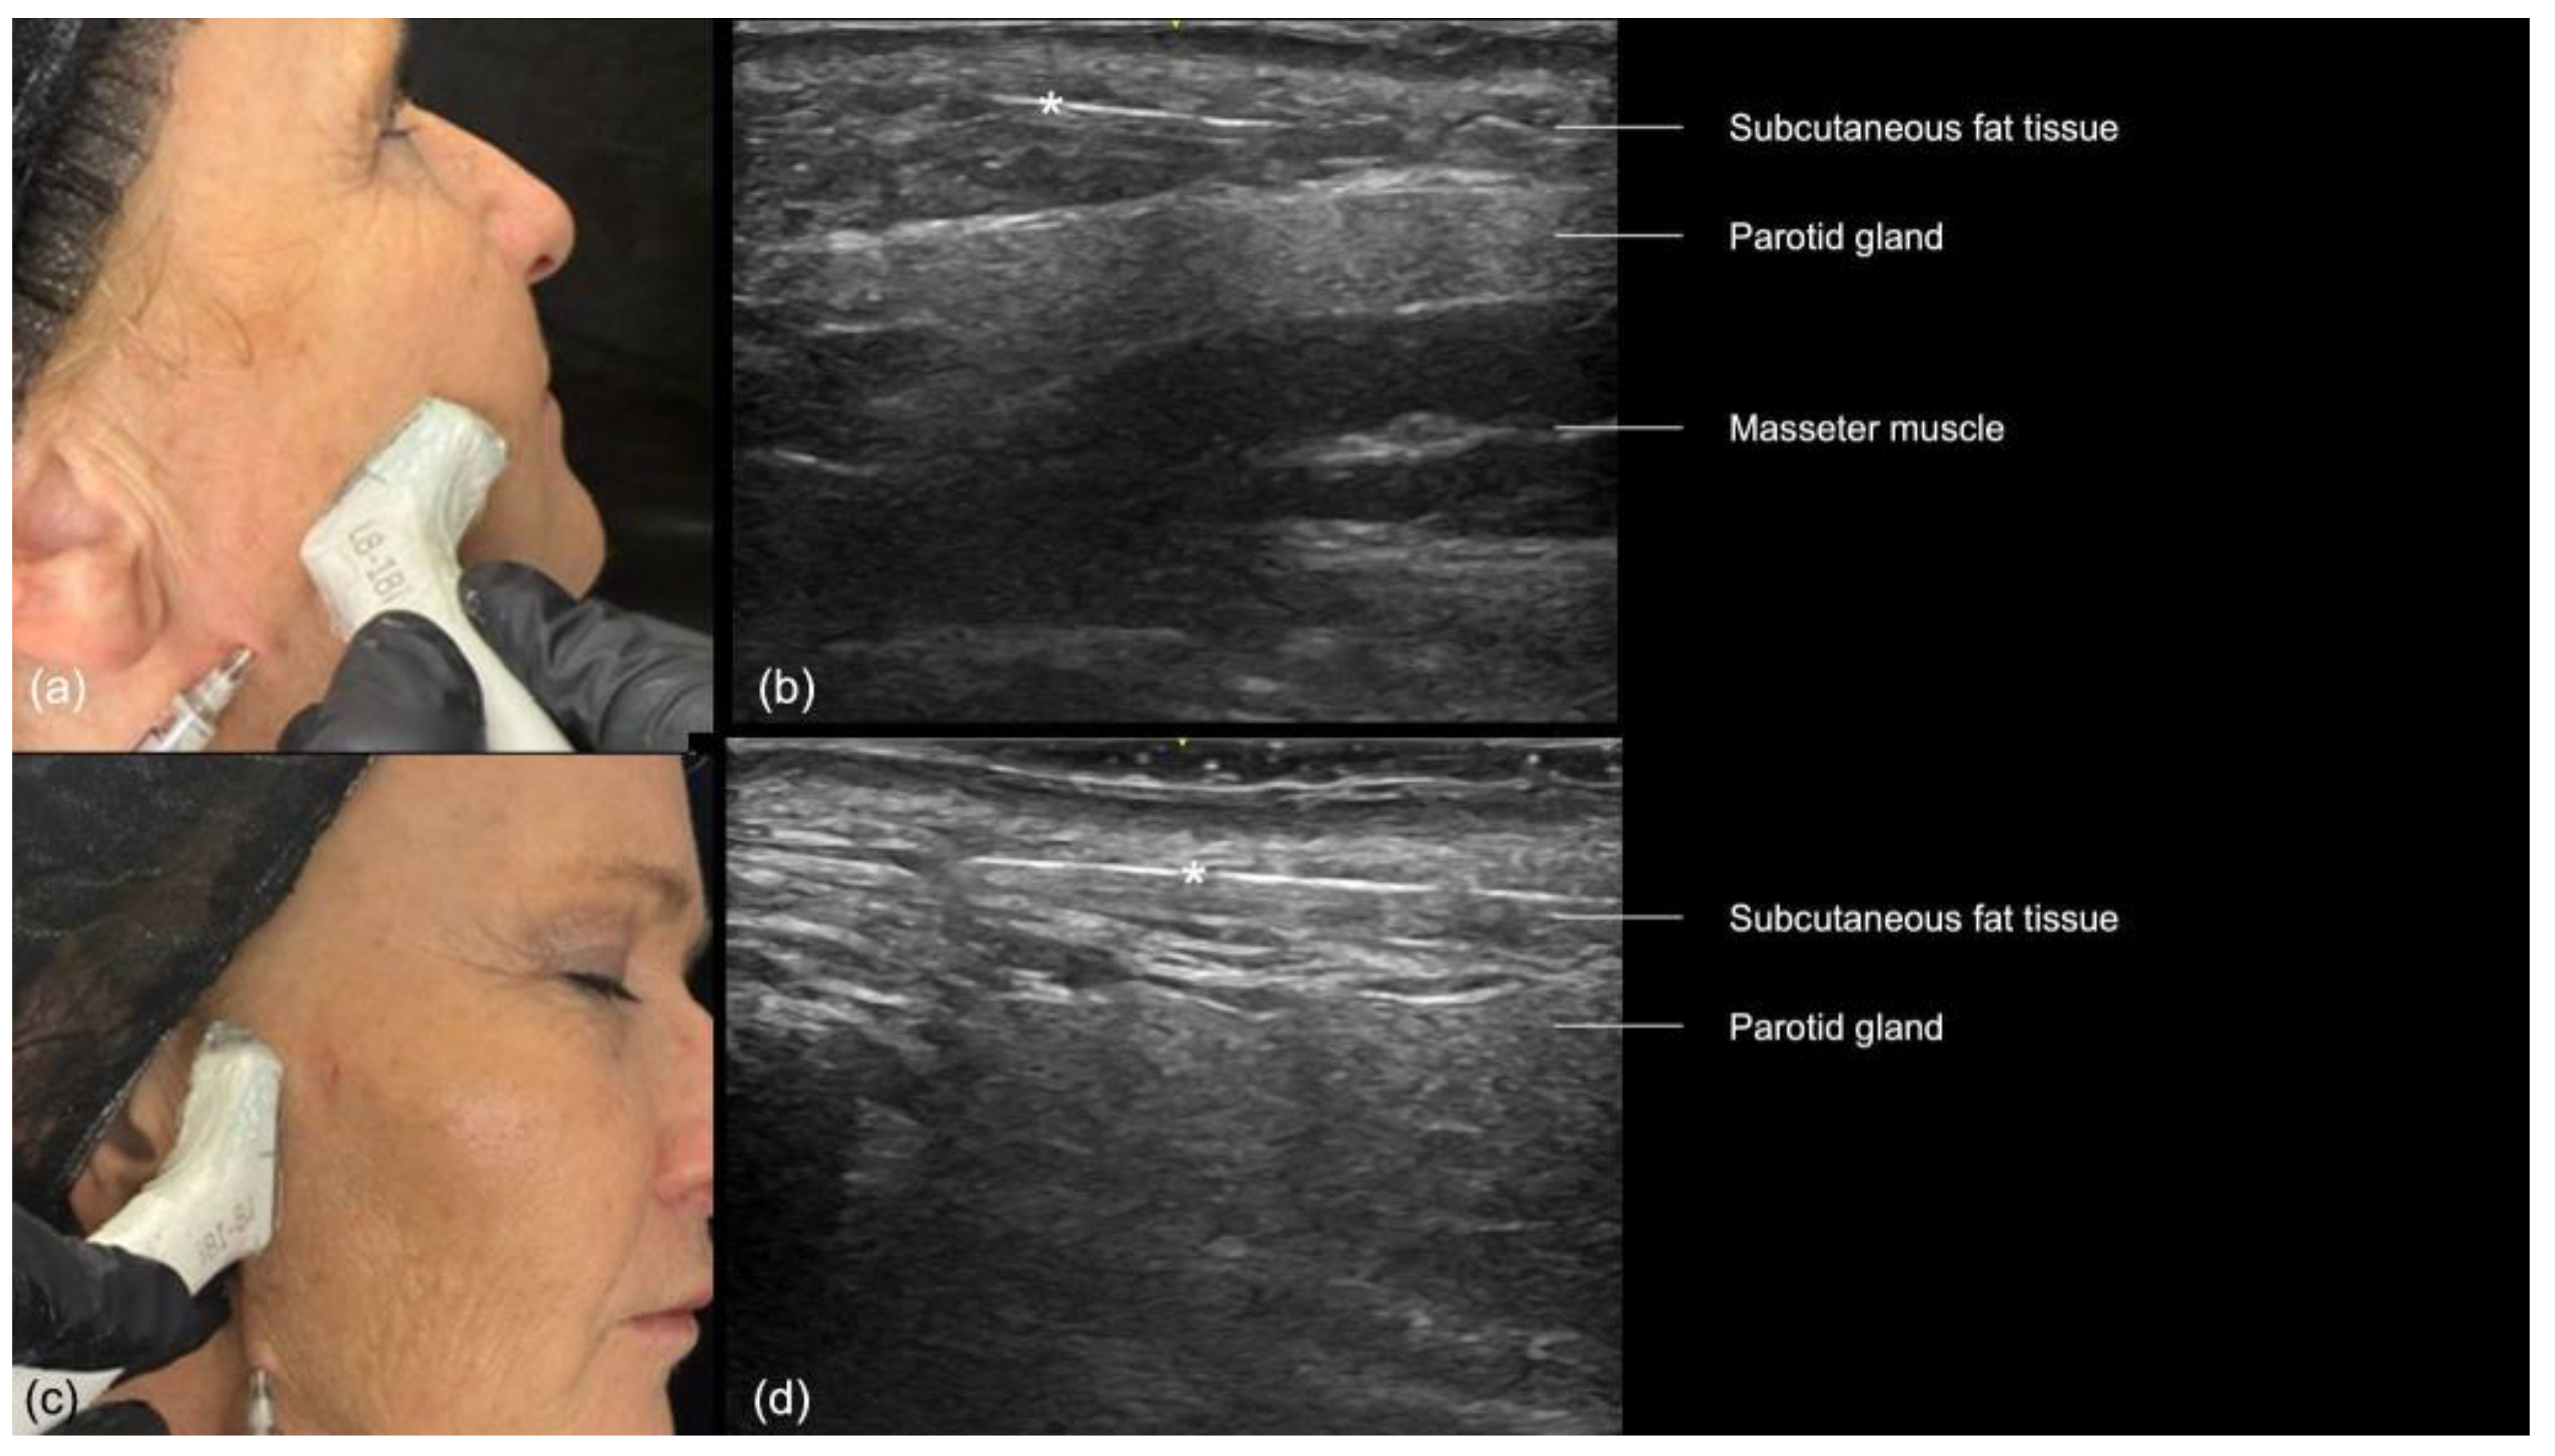

- Preauricular Region